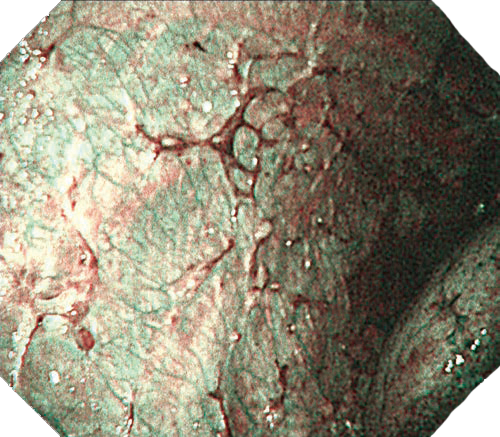

NBI

NBIは粘膜表層の血管走行が強調表示され、高精度な診断をサポートします。新しいスコープではより精細な血管構造の観察に貢献します。